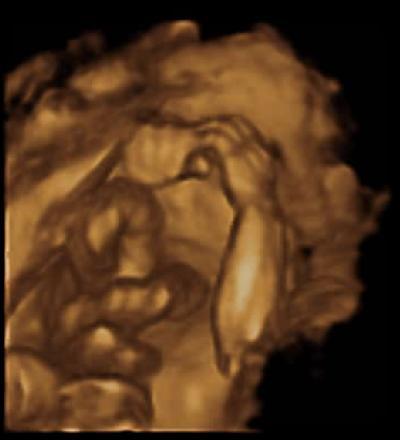

Und hier noch ein schönes US- Bild. :-) Voll die kleine Stupsnase ...

Bild zu

Hallo, das ist ja wirklich eine süße Stupsnase Die Nase unserer Kleinen war auf einem ähnlichen Seitenprofil-Bild fast doppelt so groß... der Kommentar meiner Mutter dazu: Mach dir keine Sorgen, die wachsen schubweise LG, Sabine